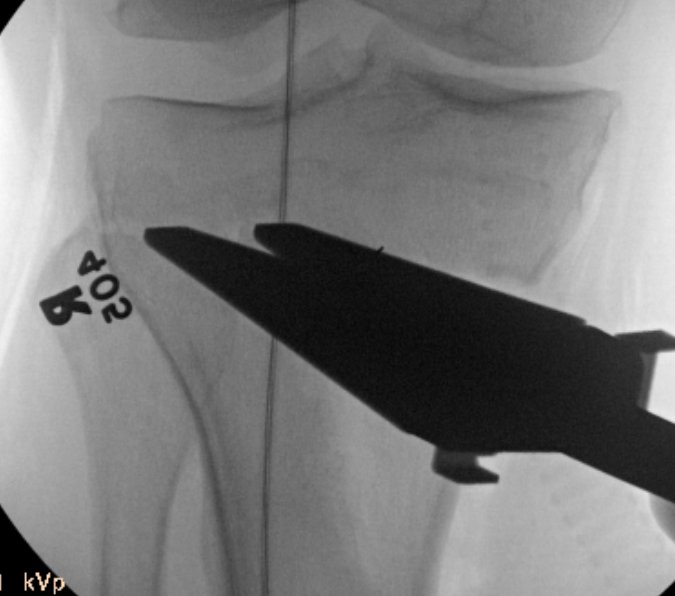

Stabilisation

- locking plates

- +/- autograft / allograft / synthetic bone graft